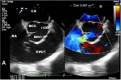

Case presentation: In this case report, we describe a 23-year-old patient with an acute onset of chest pain, shortness of breath, palpitations and dizziness starting 2 days prior to presentation to the emergency department. The patient was initially treated for presumed pulmonary embolism overnight while awaiting CTPA the next morning. However, further examination by the inpatient medical team demonstrated a continuous machinery cardiac murmur. Subsequent echocardiography demonstrated an acutely ruptured SVA with shunting to the right atrium. Emergency surgical repair resulted in an excellent outcome for the patient.